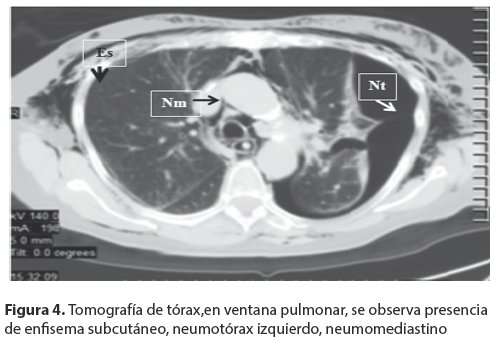

<body><![CDATA[<p align="justify"><a name="f2"></a></p>     <p align="center"><img src="/img/revistas/gmb/v37n1/a10_figura_02.jpg" width="501" height="431"></p>     <p align="justify"><font face="Verdana" size="2">La tomografía computarizada (TC); Scout (<a href="#f3">Fig. 3</a>) confirma los hallazgos anteriores, enfisema de la pared del toraco-abdominal, neumomediastino, neumotórax izquierdo, neumoperitoneo. </font></p>     <p align="justify"><a name="f3"></a></p>     <p align="center"><img src="/img/revistas/gmb/v37n1/a10_figura_03.jpg" width="503" height="448"></p>     <p align="justify"><font face="Verdana" size="2">En la TC simple de tórax en ventana mediastinica (<a href="#f4">Fig. 4</a>) se observa enfisema subcutáneo importante de la pared del tórax, neumotórax izquierdo, neumomediastino. </font></p>     <p align="justify"><a name="f5"></a></p>     <p align="center"><img src="/img/revistas/gmb/v37n1/a10_figura_04.jpg" width="498" height="343"></p>     <p align="justify"><font face="Verdana" size="2">TC de abdomen (<a href="#f5">Fig. 5</a>), se observa, enfisema subcutáneo (Es) plastrón periduodenal (Pp), pneumoperitoneo (Np) y retroneumoperitoneo (Rnp). Con la sospecha clí</font><font face="Verdana" size="2">nica e imagenológica de perforación de víscera hueca, se somete a la paciente a laparotomía exploradora de urgencia, con hallazgo de perforación del duodeno y plastrón periduodenal. Se realiza la reparación per prima, mediante duodenorrafia y evacuación de la colección y drenaje del mismo.</font></p>     <p align="justify"><a name="f5"></a></p>     ]]></body>